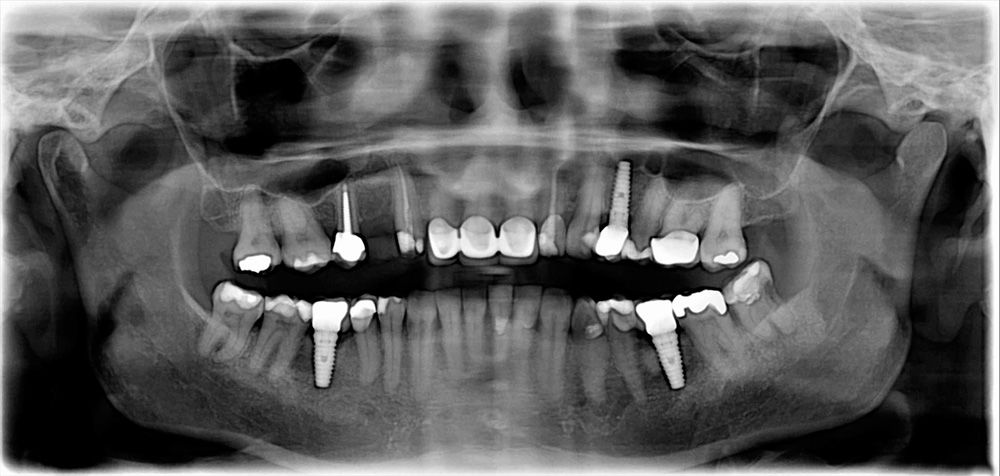

Dental implants offer a wide range of benefits, making them a popular choice for replacing missing teeth. For most patients, dental implant treatment can take up to six months from the initial consultation to the placement of their final restoration. For patients who need preparatory treatments such as bone grafting, the dental implant timeline will be longer.

For implants to be successful, they need healthy, sufficient bone tissue in your jaw that can integrate with the implants. If your jaw has shrunk after tooth loss, bone grafting may be necessary to restore sufficient bone density before implant placement.

After the implant placement, your jawbone will need to heal before the final prosthetic is placed. This healing period usually takes four to six months. During this time, your jawbone tissue will grow around the implant, securing it into place. This is known as osseointegration. After osseointegration, the dentist can place abutments.

An abutment is the connector piece between the dental implant and the dental restoration. Once your implant has successfully fused with the bone tissue, your doctor will attach the abutment during a second minor surgery in our Lake Jackson, TX, office.

In your final appointment, your crown, bridge, or denture will be attached to the abutment(s). The restoration cannot be placed unless the jaw bone and gum tissue are fully healed.